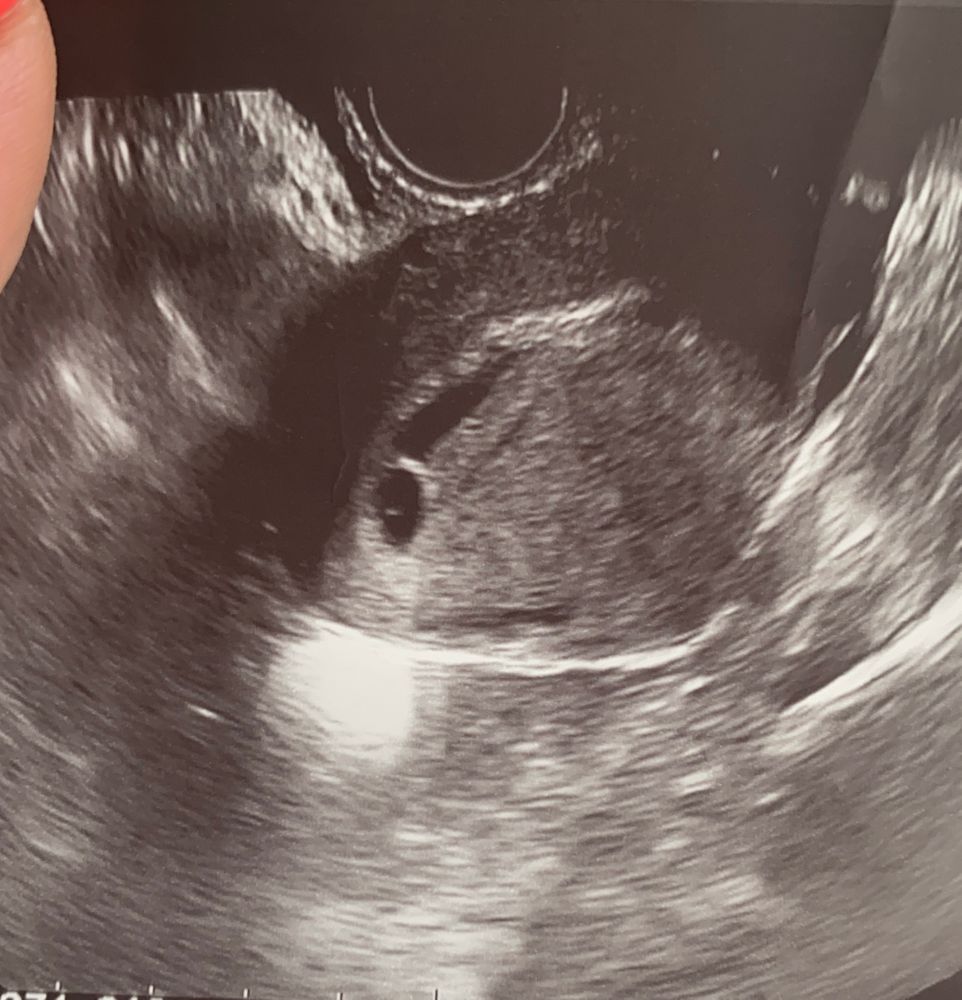

Подскажите, у кого кровила шейка при беременности? И из за чего это может быть? Срок 5-6 недель.

Лежу уже три дня, в первый день были выделения с кровью, не много, только на бумаге оставались, сказали что шейка. Прошло два дня, опять появились выделения, сегодня меня два врача посмотрели, оба говорят что это шейкая, но при этом ничего не назначают, сказали само пройдёт, но я все равно переживаю, плюс колит, то справа, то слева в районе лобка